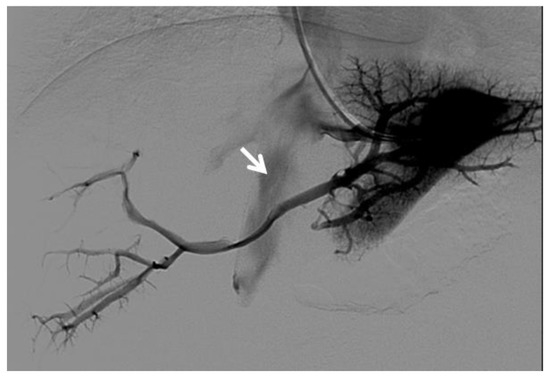

CT provides a better assessment of thrombus extension within the portal venous system than CDUS, because of its higher sensitivity and accuracy than CDUS for identifying thrombosis of the SMV and splenic vein [35]. If the SMV is involved by thrombosis, thinning of the intestinal wall or lack of mucosal enhancement of a thickened intestinal wall after contrast injection are further pieces of evidence for intestinal infarction [28] (Figure 6).

Figure 6.

CT of a 39-year-old female with no previous relevant clinical history, who presented with an intense acute abdominal pain. (a) Portal phase axial CT image shows acute massive thrombosis of left and right intrahepatic portal branches (arrows). Portal phase axial (b) and coronal (c) CT images show the extension of the thrombus to the superior mesenteric vein (arrow). No signs of intestinal infarction were present, and the patient was submitted to transjugular intrahepatic portosystemic shunt placement and mechanical thrombectomy.